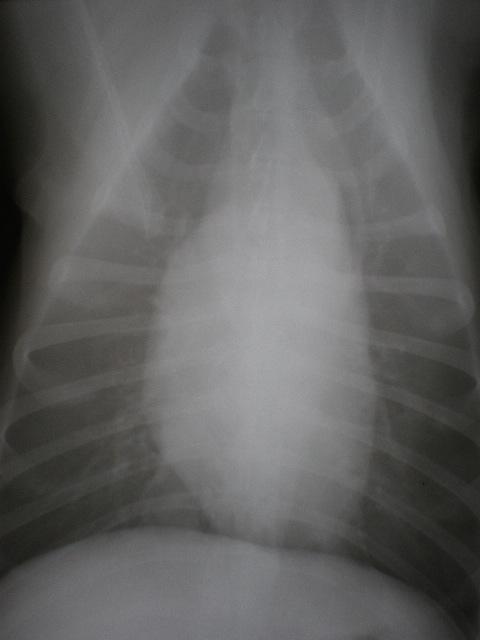

An 11-year-old MN Labrador retriever was prestented for excercise intolerance, lethargy, depression, vomiting and diarrhea. The physical exam was unremarkable other than a grade 2 left sided heart mumur at the heart base and irregular heart beat with pulse deficits. CBC, CHEM, UA, and acth stim were all normal.